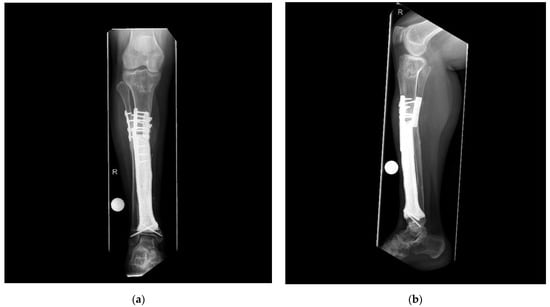

In the four patients—reconstructed using custom-made 3D-printed intercalary megaendoprostheses with a highly cancellous implant surface—distal tibia resection and below-knee amputation were avoided in all cases (Figure 3).

The first patient reconstructed using a highly cancellous 3D-printed monobloc intercalary tibia implant developed an incomplete non-union at the proximal bone-implant interface (Henderson Type 3—structural failure). Two extracortical plates with supplementary interlocking screws bridging the bone-implant interface were used to anchor the implant to the proximal tibial diaphysis without a central stem. This anchorage design was chosen to allow filling the hollow implant body with autologous iliac crest graft (Figure 5). Operative revision and additional plating of the bone implant interface while retaining the original implant were performed 9 months after primary reconstruction (Figure 6). In addition, the ipsilateral fibula was osteotomized and fixed to the tibial column using screw osteosyntheses after roughening the facing bone cortices to encourage bone union. A hypertrophic pseudarthrosis recurred at the tibial bone-implant interface while the fibular transfer consolidated and continues to stabilize the reconstruction by taking part of the load. The patient currently has full weight bearing using a light brace and declines further operative revision as her activities of daily life are not impaired and she has no athletic ambitions. Implant design has been adapted to include a central stem and solid implant body at the proximal bone-implant interface. After this alteration, non-union and hypertrophic pseudarthrosis were avoided in later patients.

Figure 5. Patient #1: Computed tomography scan 43 months after primary reconstruction: (a,b) coronar view of the implant with the depiction of the bone graft-loaded hollow implant cavity and persistent non-union of the proximal implant-bone interface.

Figure 6. Patient #1: Postoperative radiographs after osteosynthetic plating of the proximal implant-bone interface (a) a.p. view; (b) lateral view. R means right.